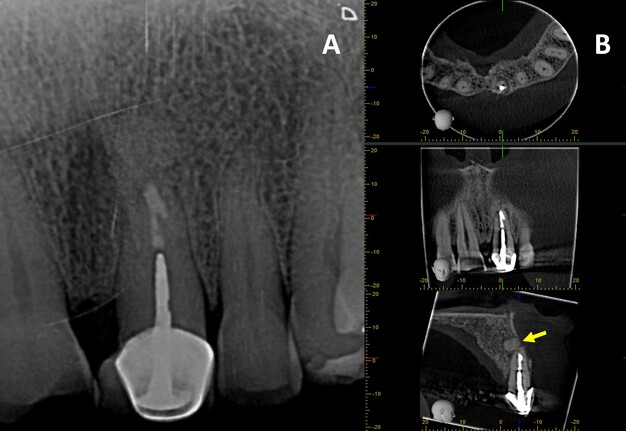

Finally, guided tissue regeneration was carried out using [1g] Quirubone bone graft with particle size [0.25-0.5 mm] (Cellstech, Itagüí, Colombia) and Quirumatriz membrane [15 x 20 mm] (Cellstech, Itagüí, Colombia) (Fig 2-M and 2-N). The flap was repositioned and sutured with resorbable Vicryl 5/0 (Vicryl Plus, Ethicon, India) (Fig 2-O). Postoperative care included amoxicillin [875mg/12h/5days], meloxicam [7.5mg/12h/3days], and mouth rinses with chlorhexidine [0.2%] (Clorhexol, Farpaq, Cali, Colombia) 10 ml-rinse for 60 s twice-a-day (every 12 h) for 7 days. Radiographic and tomographic assessment at eight months demonstrated ongoing healing of the affected periapical tissues. Furthermore, it was observed that the ultrasonic retropreparation did not follow the original trajectory of the root canal, as a slight deviation towards the distal wall was noted. In addition, the retrograde obturation material remained well positioned throughout the follow-up period, thereby supporting the favourable progression of periapical tissue repair (Fig 3 A-B).

CBCT has been recommended for the diagnosis, planning and follow-up in endodontics, due to its three-dimensional imaging, which overcomes the limitations of traditional periapical radiograph (PR) [10, 11]. In this case, CBCT identified a periapical lesion that was not visible on PR and enabled more precise surgical planning. Furthermore, the tomographic follow-up findings suggested ongoing periapical healing. Compared to PR, it may have been mistakenly considered a complete healing, which supports the use of CBCT for longer-term follow-up of this case.

In addition to its superior spatial resolution, CBCT provides volumetric data that allow clinicians to assess the extent and morphology of periapical lesions with greater accuracy. This is particularly valuable in cases where conventional radiographs fail to reveal subtle changes in bone density or lesion progression. The ability to visualise anatomical structures in multiple planes enhances diagnostic confidence and facilitates the identification of complex root canal systems, accessory canals, and bone fenestrations. Moreover, CBCT is instrumental in monitoring the healing process post-operatively, as it can detect early signs of bone regeneration and residual pathology that may not be apparent on two-dimensional images. The literature consistently supports the integration of CBCT into routine endodontic practice, especially for cases requiring detailed assessment and long-term follow-up, thereby improving clinical outcomes and reducing the risk of misdiagnosis [11].